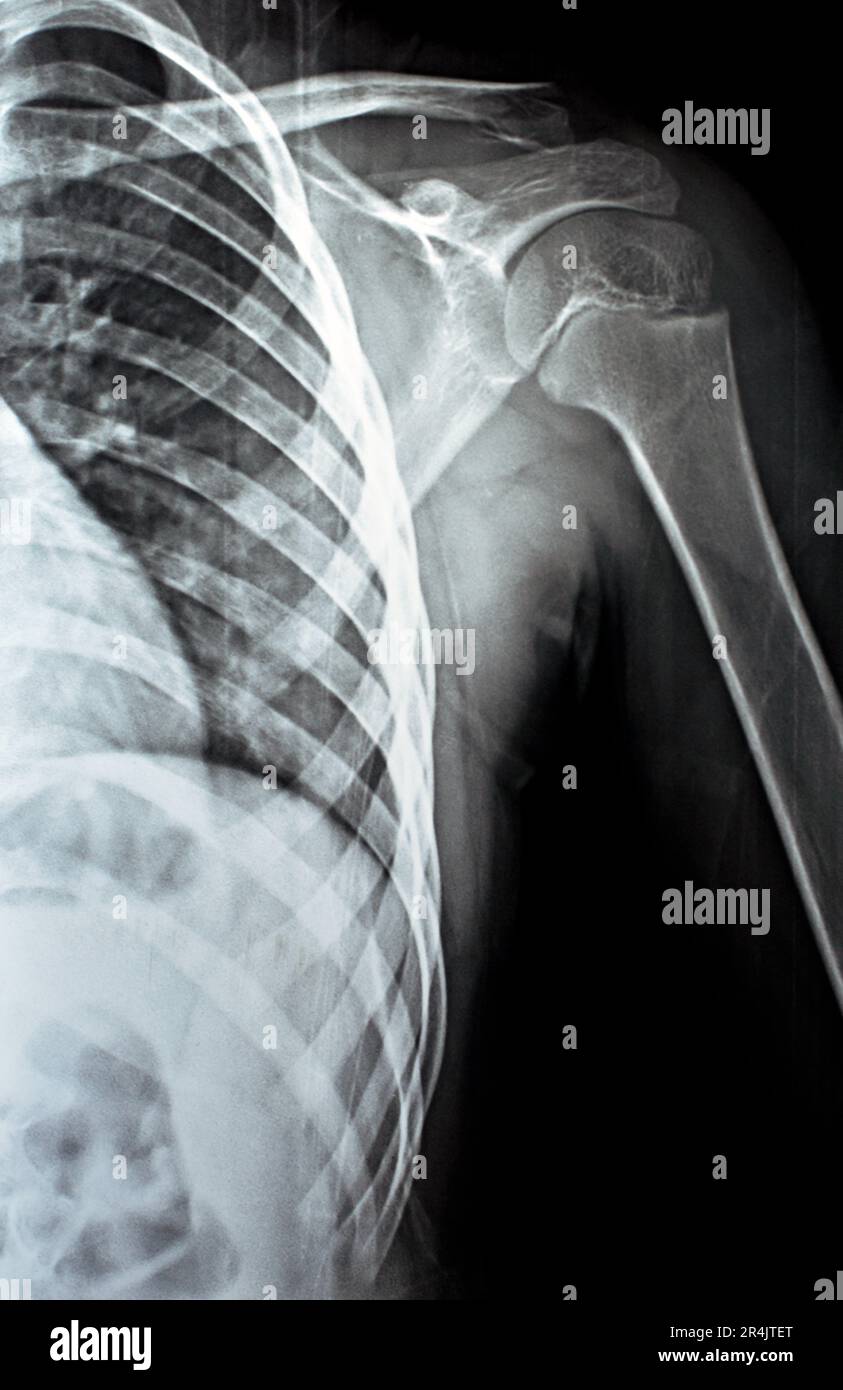

X Ray Shoulder Lateral Position . The projection demonstrates the shoulder in its natural. Lateral/scapula y view (named due to the. the shoulder series is fundamentally composed of two orthogonal views of the glenohumeral joint including. rotate into an anterior oblique position. Average patient will be in a 45 ° to 60 ° anterior oblique position. the shoulder ap view is a standard projection that makes up the two view shoulder series.

The projection demonstrates the shoulder in its natural. Average patient will be in a 45 ° to 60 ° anterior oblique position. rotate into an anterior oblique position. the shoulder series is fundamentally composed of two orthogonal views of the glenohumeral joint including. Lateral/scapula y view (named due to the. the shoulder ap view is a standard projection that makes up the two view shoulder series.